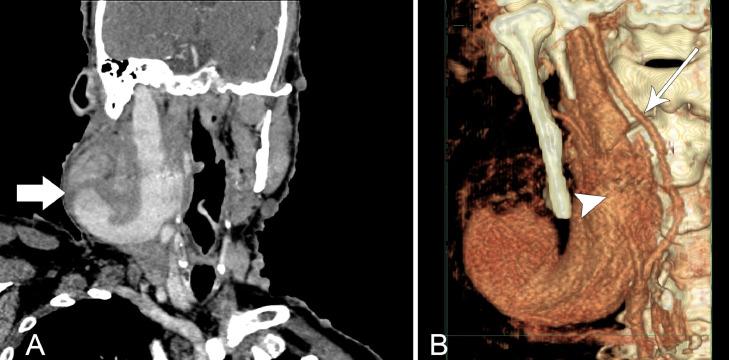

Neurofibromatosis Type 1 (NF1) is a rare autosomal dominant disorder that has a wide array of clinical manifestations. NF1 Vasculopathies constitute 0.4% to 6.4% of the findings and they often develop in the arterial circulation while venous involvement is rare. We present a case of a 73-year-old male with NF1 with an incidental finding of right neck swelling for 2 months. Different radiological modalities were performed, identifying the lesion as an internal jugular vein aneurysm. The patient was managed conservatively as he was asymptomatic in relation to the swelling. NF1 venous vasculopathies are rare but they have detrimental consequences such as rupture and severe hemorrhage in view of the fragility of the aneurysmal wall and the infiltration of the neurofibroma into the vessel. Hence, high clinical suspicion and selective imaging and follow-up is advisable for physicians.

1型神经纤维瘤病(NF1)是一种罕见的常染色体显性疾病,具有广泛的临床表现。NF1血管病变占所有检查结果的0.4%至6.4%,常发生于动脉循环,而静脉受累罕见。我们报告一例73岁男性NF1患者,偶然发现右颈部肿胀2个月。进行了不同的影像学检查,确定病变为颈内静脉动脉瘤。由于患者肿胀部位无症状,因此采取了保守治疗。鉴于动脉瘤壁的脆弱性以及神经纤维瘤向血管内浸润,NF1静脉血管病变虽罕见,但可导致破裂和严重出血等不良后果。因此,医生应保持高度临床怀疑,并进行选择性影像学检查和随访。